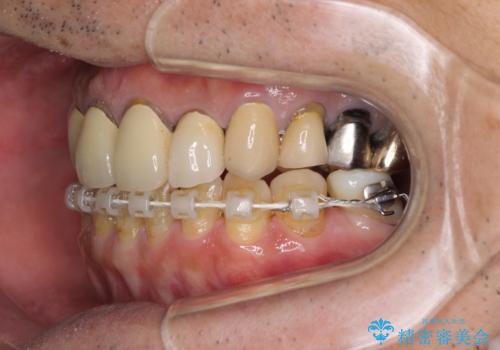

- 抜歯した歯や抜歯が必要と思われる歯を放置したため、奥歯に不快を感じているとのことで来院された患者様です。

右下は奥歯が抜歯したスペースを塞いでしまい、左下はブリッジの支台歯の1つが破折している状態でした。

また、下顎前歯にはスペースがあり、コンポジットレジンでスペースを閉じている状態だったので、前歯のスペースを解消しつつ、奥歯にスペースを獲得するよう矯正治療を行うこととしました。

並行して左下にはインプラントを埋入し、上顎臼歯部の気になる部分も根管治療などを進めて行き、矯正治療を終えると同時に補綴治療を行うこととしました。